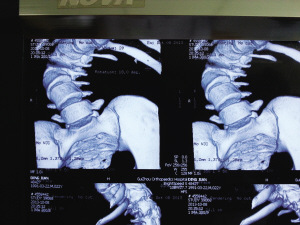

術(shù)前,小健脊柱側(cè)彎嚴(yán)重。

術(shù)后“長(zhǎng)高”了12公分。

今年1月,小健感覺(jué)身體不適,便在親友陪同下來(lái)到省骨科醫(yī)院。經(jīng)檢查,醫(yī)生發(fā)現(xiàn)小健脊柱后凸彎近150度,側(cè)凸近130度,肺功能受損達(dá)30%。因小健已經(jīng)22歲,脊柱生長(zhǎng)已經(jīng)停止,十分僵硬,錯(cuò)過(guò)了最佳治療期,只能做脊柱側(cè)彎矯正手術(shù),但該手術(shù)費(fèi)用高,難度大。

8個(gè)小時(shí)的手術(shù)中,小健共被植入19根金屬釘。手術(shù)成功后,小健背部包塊不見(jiàn)了,身高從156公分“躥”到168公分。昨日,出院后的小健來(lái)到醫(yī)院復(fù)查,恢復(fù)結(jié)果良好。